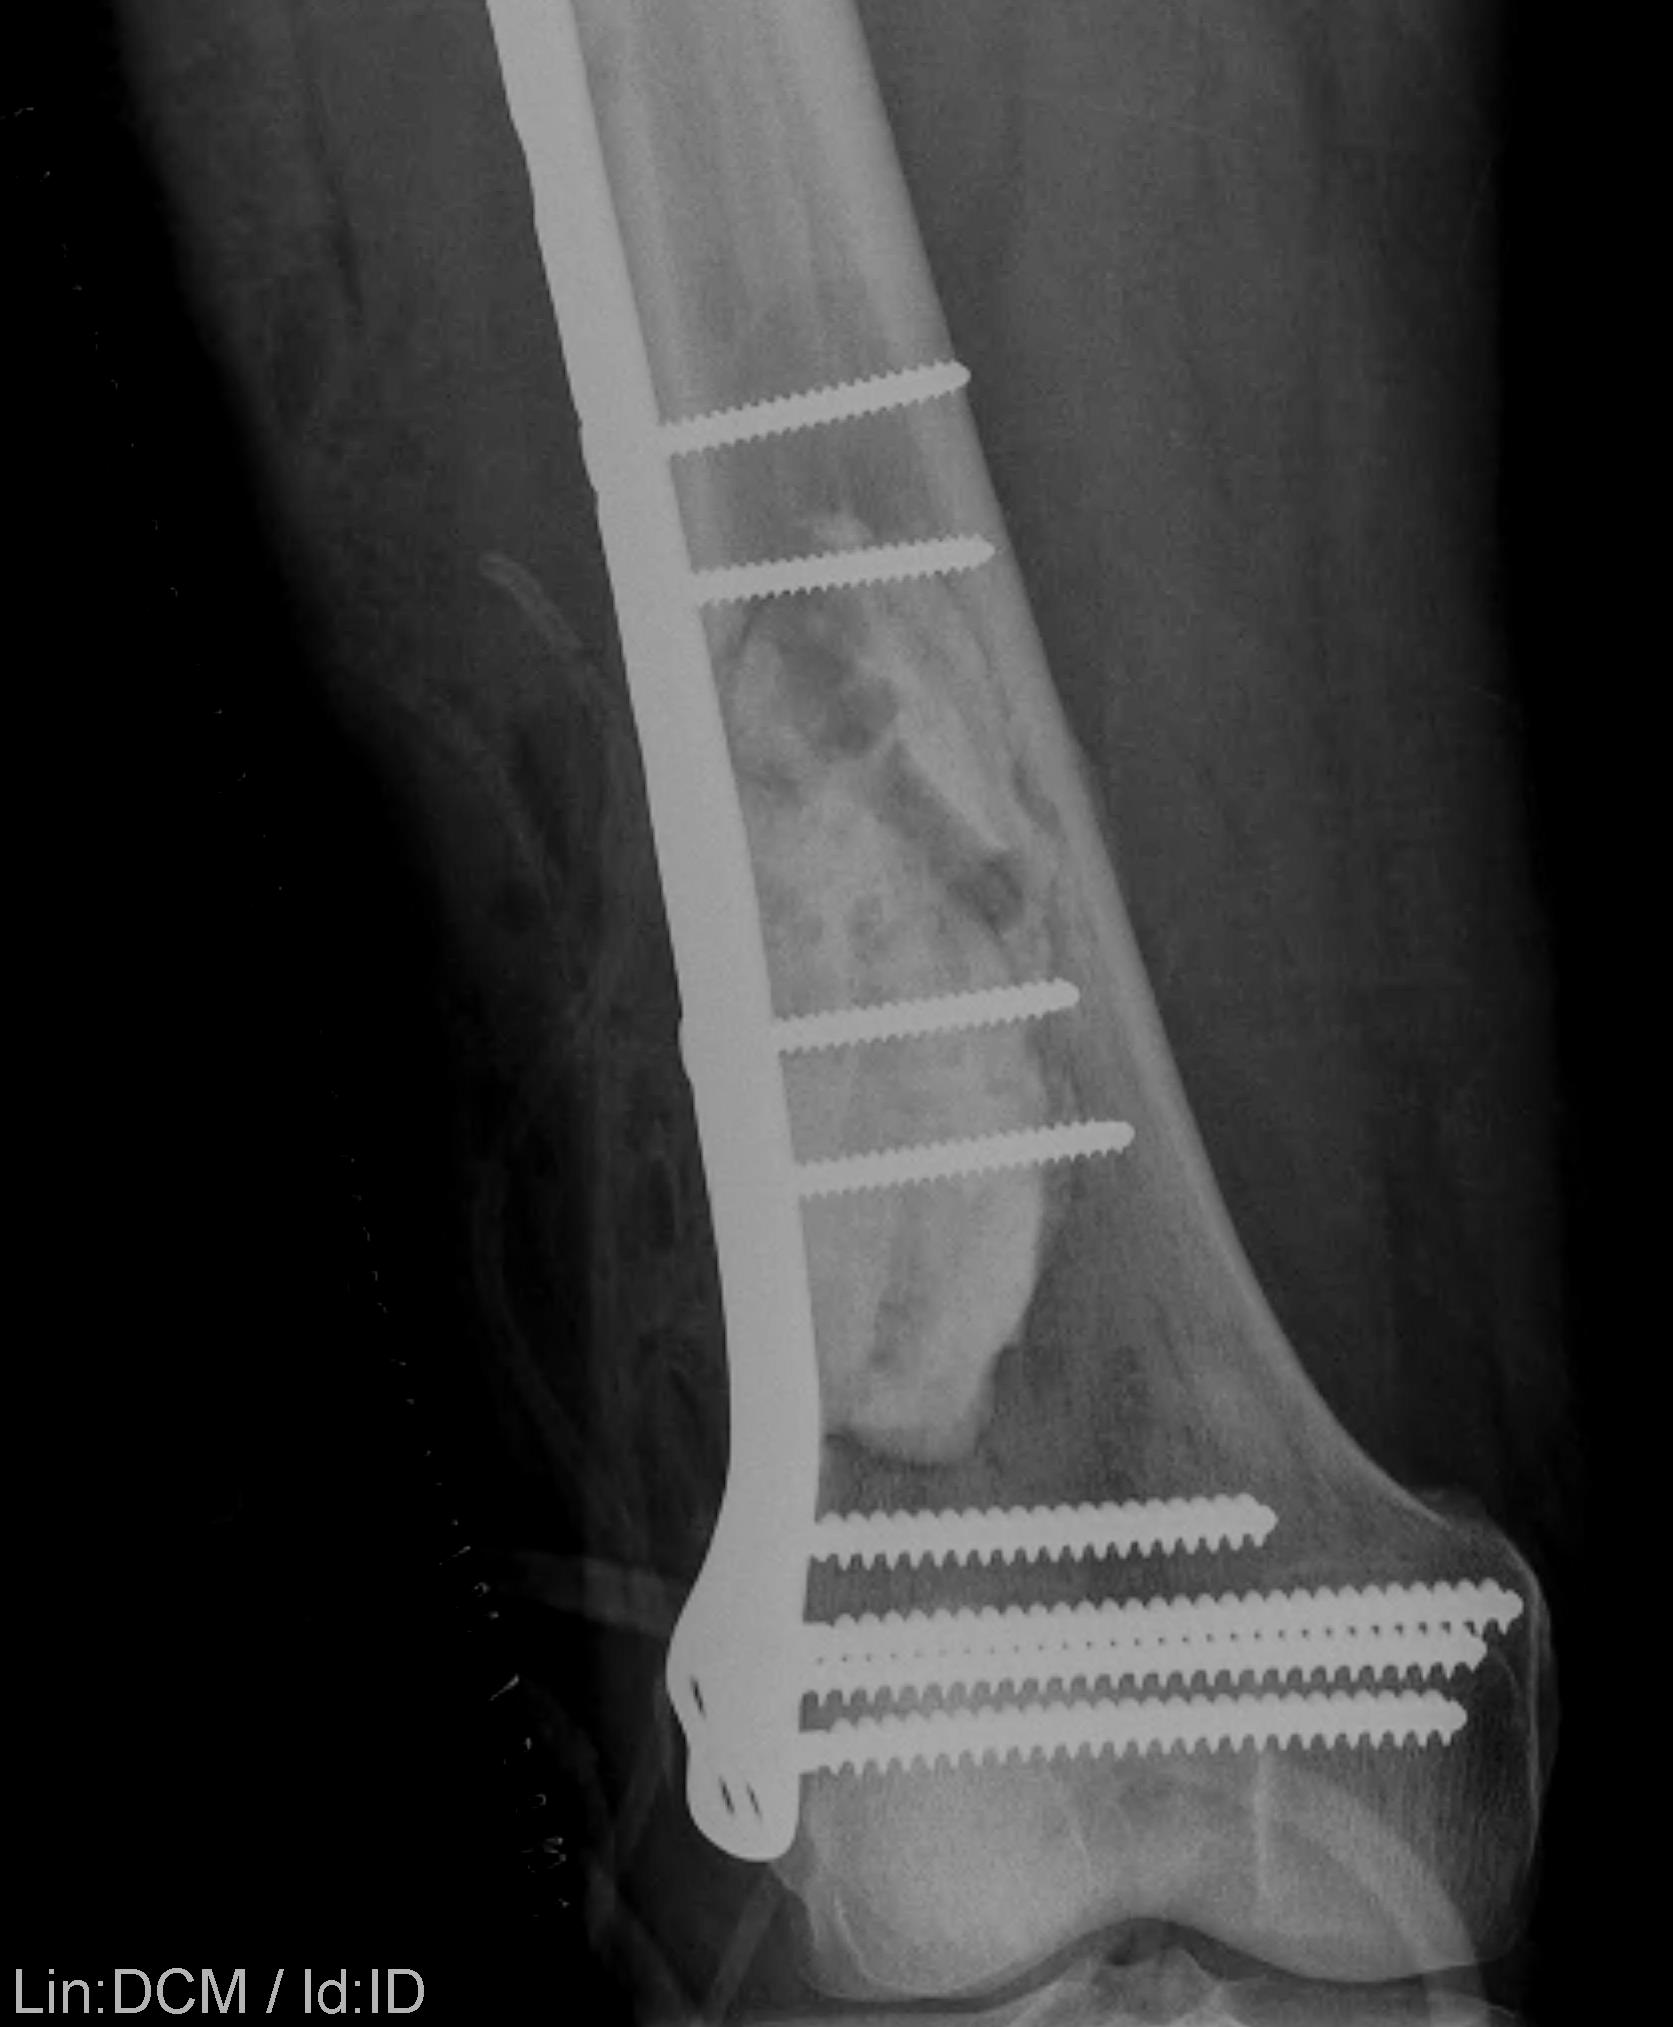

Supracondylar Femur

Options

Plate / dual plate

Retrograde nail

Modular knee prosthesis